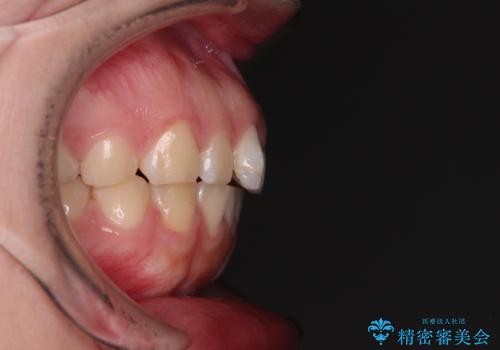

- 出っ歯と口の閉じにくさ、デコボコを気にして来院された患者様です。

口元の突出感を改善するため、上下左右第一小臼歯4本の抜歯を行い、ワイヤー装置による矯正治療を行うこととしました。

抜歯矯正を行ったことで、顎先のつっぱり感や口元の閉じにくさを解消することができました。